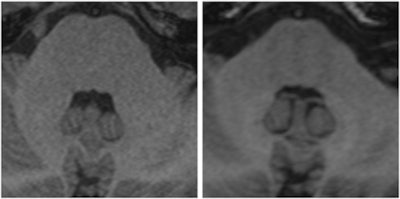

Two images of a patient prior to (left) and after (right) nine injections of the linear gadolinium-based contrast agent Magnevist. The image prior to injection shows no hyperintensities displayed in the dentate nucleus, while a clear signal intensity increase in the dentate nucleus becomes visible after nine injections of Magnevist. Images courtesy of Dr. Alexander Radbruch, head of neuro-oncologic imaging at the University Hospital Heidelberg in Germany.At today's session, he intends to speak about the preclinical data around the recent discovery that gadolinium deposits in the body -- a finding that has rattled radiologists.